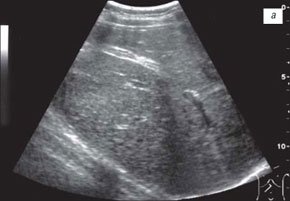

При ультразвуковом исследовании гепатобилиарной системы у всех детей с течением муковисцидоза средней тяжести отмечались различные изменения желчного пузыря: у 8 пациентов его размеры были увеличены, у 4 детей - уменьшены, у 3 - желчный пузырь не визуализировался, у 2 детей на эхограмме в области проекции желчного пузыря определялся гиперэхогенный тяж, что могло быть связано с его склерозированием (рис. 1а). В группе детей с тяжелым течением муковисцидоза увеличение размеров желчного пузыря отмечено лишь у 3 детей, уменьшение его размеров - у 6 больных, не визуализировался - у 3 детей и у 3 пациентов имели место признаки его склерозирования.

а) При муковисцидозе средней тяжести (склерозированный пузырь).